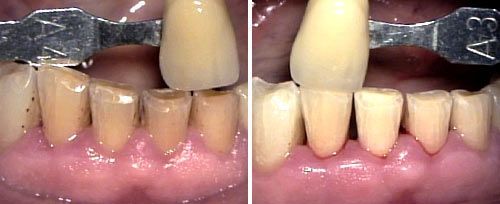

Tooth Whitening

Courtesy of: Evgeniy Mironov, DDS

Laser source: Er:YAG (2940 nm)